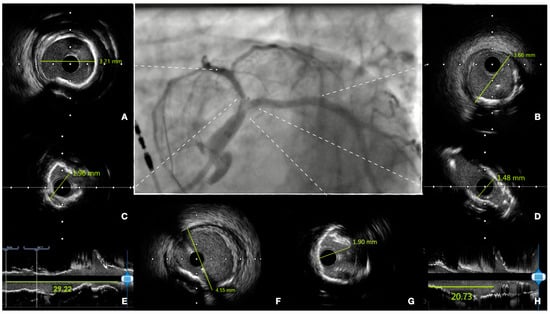

7. Technical Considerations during PCI

8. Intracoronary Imaging Guidance before, during and after PCI